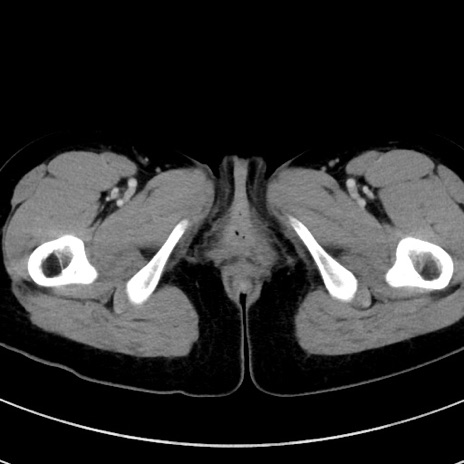

症例17(横断像)

【症例】20歳代女性

【主訴】嘔吐、下腹部痛

【現病歴】昨日夕食後に嘔吐し下腹部痛が出現。本日になっても嘔吐持続し改善しないため来院。

【身体所見】意識清明、BT 37.2℃、BP 108/67mmHg、腹部:平坦、やや硬、下腹部正中から右にかけて圧痛あり、反跳痛軽度あり、tapping pain(+)。

【データ】WBC 13600、CRP 14.94